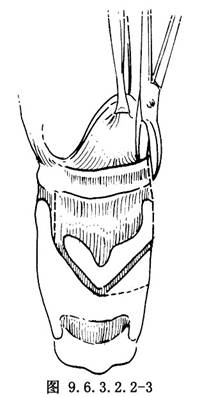

10.6 6.舌骨上入路

用電刀切斷舌骨上肌後,Allis組織鉗抓持舌骨,用軟骨剪在舌骨小角外側剪斷舌骨,向前下牽拉舌骨,用刀橫行切開舌骨會厭韌帶會厭谷黏膜進入喉咽腔,再沿舌骨兩外側向下剪開甲狀舌骨膜,即可窺見會厭(圖9.6.3.2.2-3)。